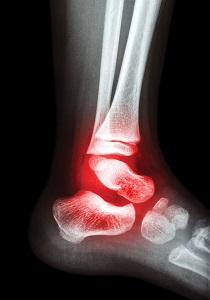

Arthritis is a disease characterized by the inflammation of the cartilage and lining of the body’s joints. Inflammation causes redness, warmth, pain and swelling. There are about 40 million Americans who suffer from arthritis. The National Institute of Arthritis and Musculoskeletal and Skin Diseases, estimates that by the year 2020, about 60 million Americans will have arthritis. The primary targets for arthritis are people over the age of 50. Arthritis is a major cause of foot pain because each foot has 33 joints that can become affected by the disease.

There are many different types of arthritis. The most common type is called osteoarthritis. Osteoarthritis causes excessive strain and the wearing away of cartilage in the joints of the foot. Movement becomes very difficult and painful. The pain and swelling worsens while standing or walking, and stiffness usually occurs after periods of rest.

Gout is another form of arthritis that also leads to foot complications. Excess uric acid crystals collect in and around the joints of the big toe. The big toe joint is commonly the focal point due to the stress and pressure it experiences during walking and other weight bearing activities. This often leads to severe pain in the big toe. Men are more likely to develop gouty arthritis than women.

Another type of arthritis is rheumatoid arthritis. It can develop at any age and there is no known cause for this condition. Rheumatoid arthritis is the most crippling form of the disease that can affect people of all ages. It can cause severe deformities of the joints with associated fatigue of the entire body. People who suffer from rheumatoid arthritis often develop severe forefoot problems such as bunions, hammer toes, claw toes, and others.

There are many causes of arthritis. Heredity plays a major role. However, arthritic symptoms can develop due to many other factors. Some of these include bacterial and viral infections, prescription and illegal drugs, traumatic injuries, and bowel disorders such as ileitis and colitis.

Forefoot problems such as hammer toes, claw toes, mallet toes, and bunions often develop as a result of arthritis, particularly Rheumatoid arthritis. Problems can also develop in the heel and ankle area due to the erosion of the involved joints.

Conservative treatment (non-surgical treatment) of the arthritic foot includes proper footwear, orthotics, and/or forefoot supports. Arthritic footwear should provide a high, wide toe box (high and wide space in the toe area). Removable insoles for fitting flexibility and the option to insert orthotics if necessary. Rocker Soles designed to facilitate ambulating (walking) and to reduce stress and pain at the ball-of-the-foot. Arthritic footwear should also accommodate swelling of the foot. Orthotics designed to provide comfort, support and extra cushioning are also recommended. Orthotics made with a material called Plastazote are often recommended because they mold to your feet to provide customized comfort. The proper footwear and orthotics will reduce pressure to provide a comfortable and healthy environment for the foot. Forefoot supports such as gel toe caps, gel toe shields, gel toe straighteners and others can often provide relief.